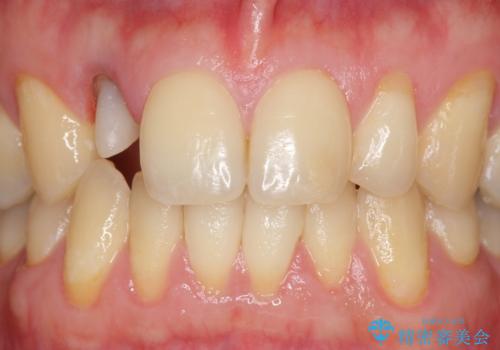

- 金属を使っていない被せ物に替えたいといらっしゃった方の症例です。

再根管治療終了後、オールセラミッククラウンによる補綴を行いました。